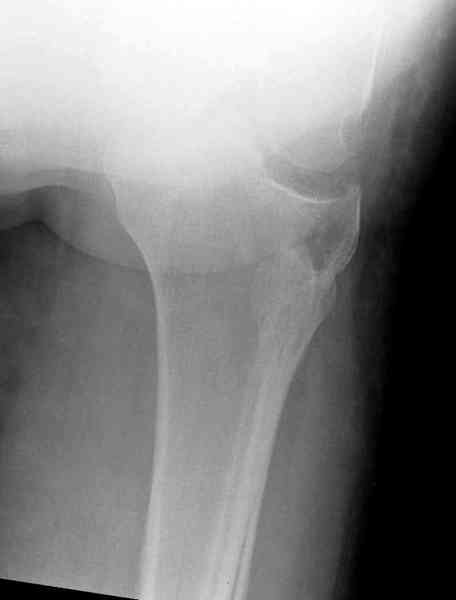

Остеосинтез при импрессионном переломе заднего отдела наружного мыщелка tibia? |

Здравствуйте, уважаемые коллеги!Подскажите, пожалуйста, какой выбрать доступ и способ фиксации при импрессионном переломе заднего отдела наружного мыщелка большеберцовой кости. Женщина 40 лет, травму получила 02.01.2008, катаясь на горных лыжах.Есть ли здесь необходимость использовать задний доступ, или можно справиться через наружный? Есть ли шансы сделать закрыто - под ЭОП через медиальное "окошко" поднять забойником суставную поврехность? Какой лучше использовать фиксатор?Спасибо.

Это техника применяется, когда имеется

центральная импрессия, а при ипрессии с краевым переломом - после приподнимания импрессии опорная (Butress) пластина, как на снимке.